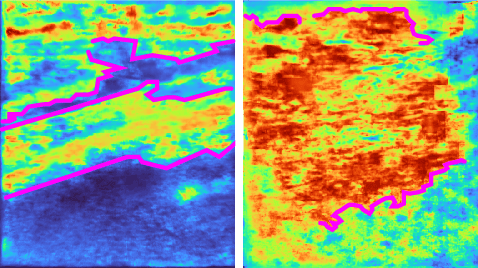

Abstract:Current methods for performing 3D reconstruction and novel view synthesis (NVS) in ultrasound imaging data often face severe artifacts when training NeRF-based approaches. The artifacts produced by current approaches differ from NeRF floaters in general scenes because of the unique nature of ultrasound capture. Furthermore, existing models fail to produce reasonable 3D reconstructions when ultrasound data is captured or obtained casually in uncontrolled environments, which is common in clinical settings. Consequently, existing reconstruction and NVS methods struggle to handle ultrasound motion, fail to capture intricate details, and cannot model transparent and reflective surfaces. In this work, we introduced NeRF-US, which incorporates 3D-geometry guidance for border probability and scattering density into NeRF training, while also utilizing ultrasound-specific rendering over traditional volume rendering. These 3D priors are learned through a diffusion model. Through experiments conducted on our new "Ultrasound in the Wild" dataset, we observed accurate, clinically plausible, artifact-free reconstructions.